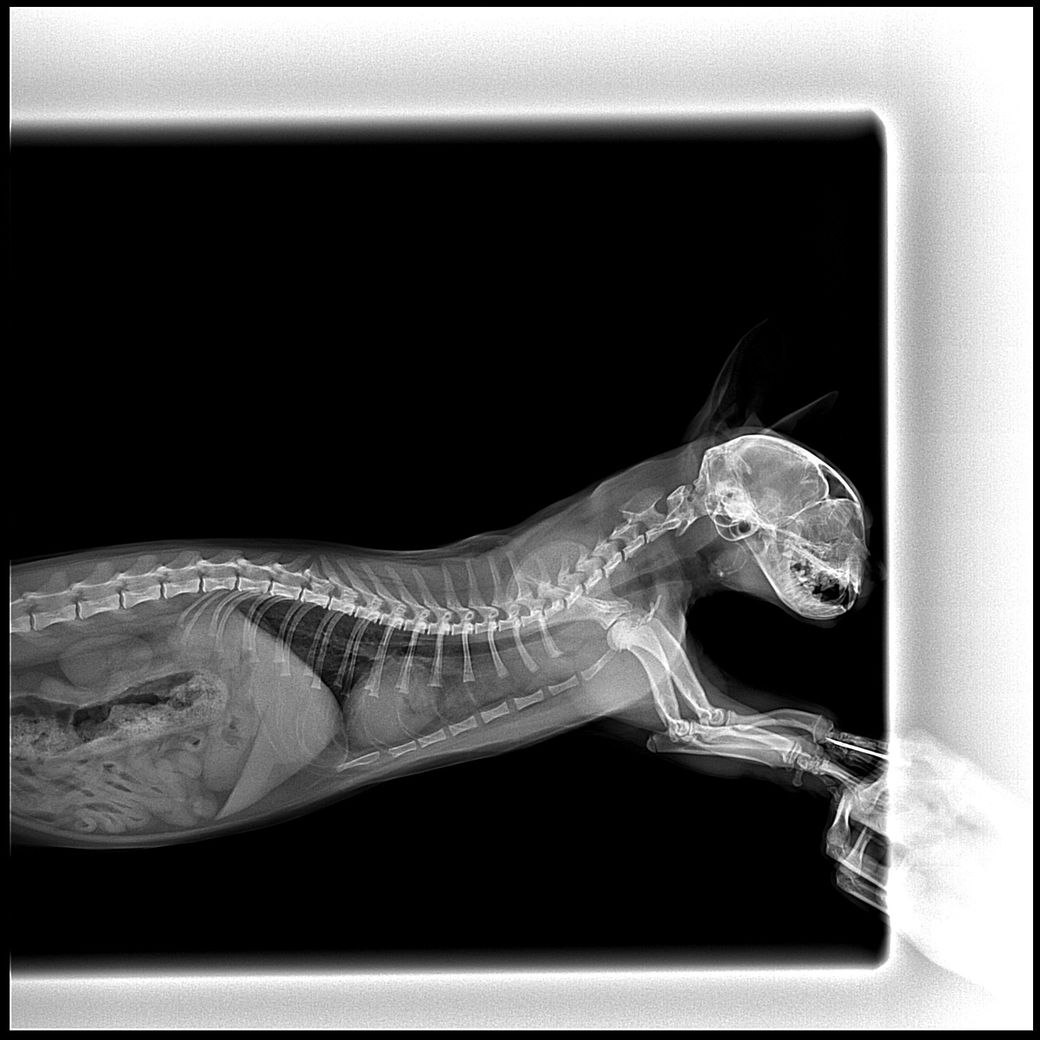

8개월된 고양이 흉부 엑스레이 촬영 후, 흉선이 작아지지 않았다는 소견을 받았습니다. 혹시 림프종이나 종격동 관련 지병일 가능성이 있을까요?

예, 종격동의 폭이 정상보다 3배 수준 이상으로 넓고, 변연이 직선형이기 때문에 종격동내 물이 차있는 상태를 의심해야 합니다. 림프종도 가능성은 있지만 환자의 연령을 고려할때 그 가능성은 낮고, 복막염이나, 식도파열, 감염성 종격동염 등의 가능성, 출혈 등을 의심해야 합니다. 주치의와 진솔한 상담 받으시기 바랍니다. 필요에 따라 CT 검사가 추천됩니다.